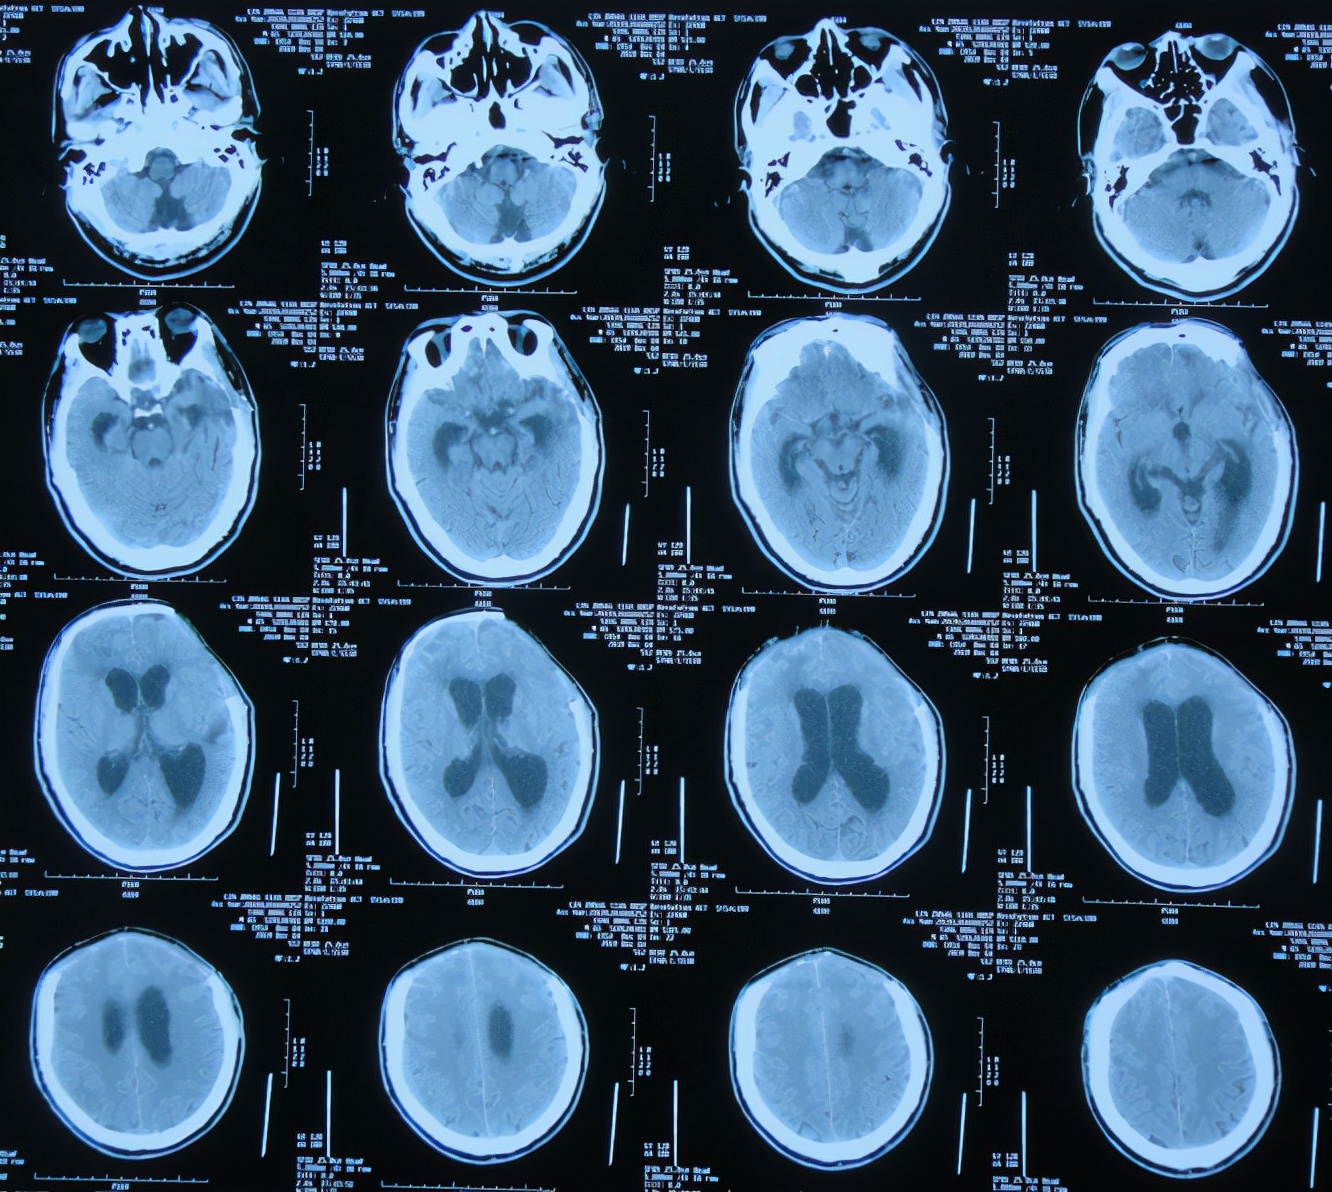

但第1家医院出院后13天即2019年12月4日,出现尿*禁失**,到当地的邯郸市临漳县某医院查头颅CT( 图-13 )后,转给给予开颅手术的医院医生,医生认为与出院时无明显变化,但之后的6天时间内出现走路不稳,大小便*禁失**加重的症状。

图-13: 2019年12月4日头颅CT

为求进一步有效治疗,于第1家医院出院后19天即2019年12月10日,住入第2家的北京某解放军的三甲医院,入院次日查头颅CT( 图-14 )后认为是脑积水。

图-14: 2019年12月11日头颅CT

入院3天即2019年12月13日,同时进行了颅骨修补术+脑室腹腔分流术。术后3天即2019年12月16日,在搀扶下可以下床走路活动,查头颅CT示颅骨修补术后+脑室引流术后状态( 图-15 )。

图-15: 2019年12月16日头颅CT

但颅骨修补术+脑室腹腔分流术后第5天即2019年12月18日,出现意识有点不清。

颅骨修补术+脑室腹腔分流术后第6天即2019年12月19日,复查头颅CT示引流管周围少量出血( 图-16 ),给予拔除头部引流,换做腰大池引流。

图-16: 2019年12月19日头颅CT

腰大池引流术后5天即2019年12月24日(颅骨修补术后11天即拔除脑室引流管后5天),查头颅CT示脑室仍扩张( 图-17 )。

图-17: 2019年12月24日头颅CT

腰大池引流术后8天即2019年12月27日(颅骨修补术后11天即拔除脑室引流管后8天),查头颅CT示脑室有缩小,积血减少( 图-18 )。

图-18: 2019年12月27日头颅CT

腰大池引流术后11天即2019年12月30日(颅骨修补术后11天即拔除脑室引流管后11天),查头颅CT示仍有脑室扩张( 图-19 )。

图-19: 2019年12月30日头颅CT

腰大池引流后13天即2020年1月1日,复查头颅CT( 图-20 )示认为积血基本吸收;给予拔除腰大池引流管。

图-20: 2020年1月1日头颅CT